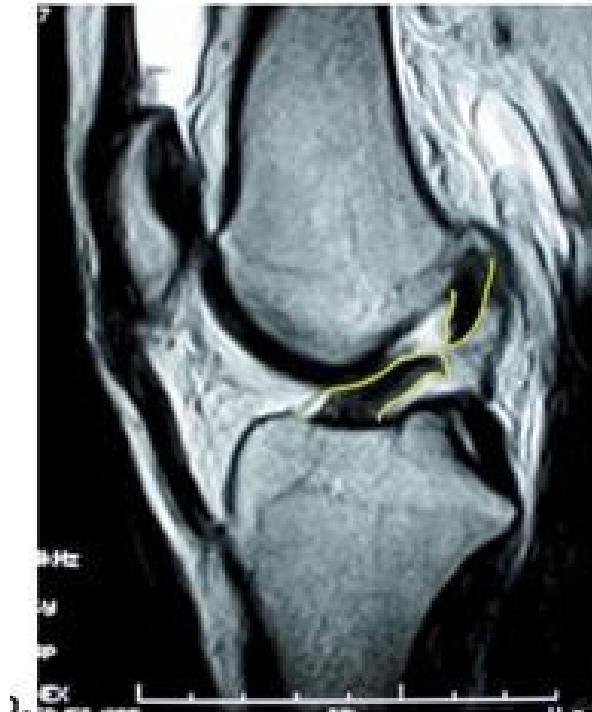

| Meniscus: McMurry’s test OR Medial & Lateral joint tenderness Apley grinding test | Assess for meniscal tears | McMurry’s test: Apley grinding test: ![]() | Click, thud, or pain during knee flexion, extension, and rotation during McMurray’s; pain during compression and rotation during Apley’s. | |